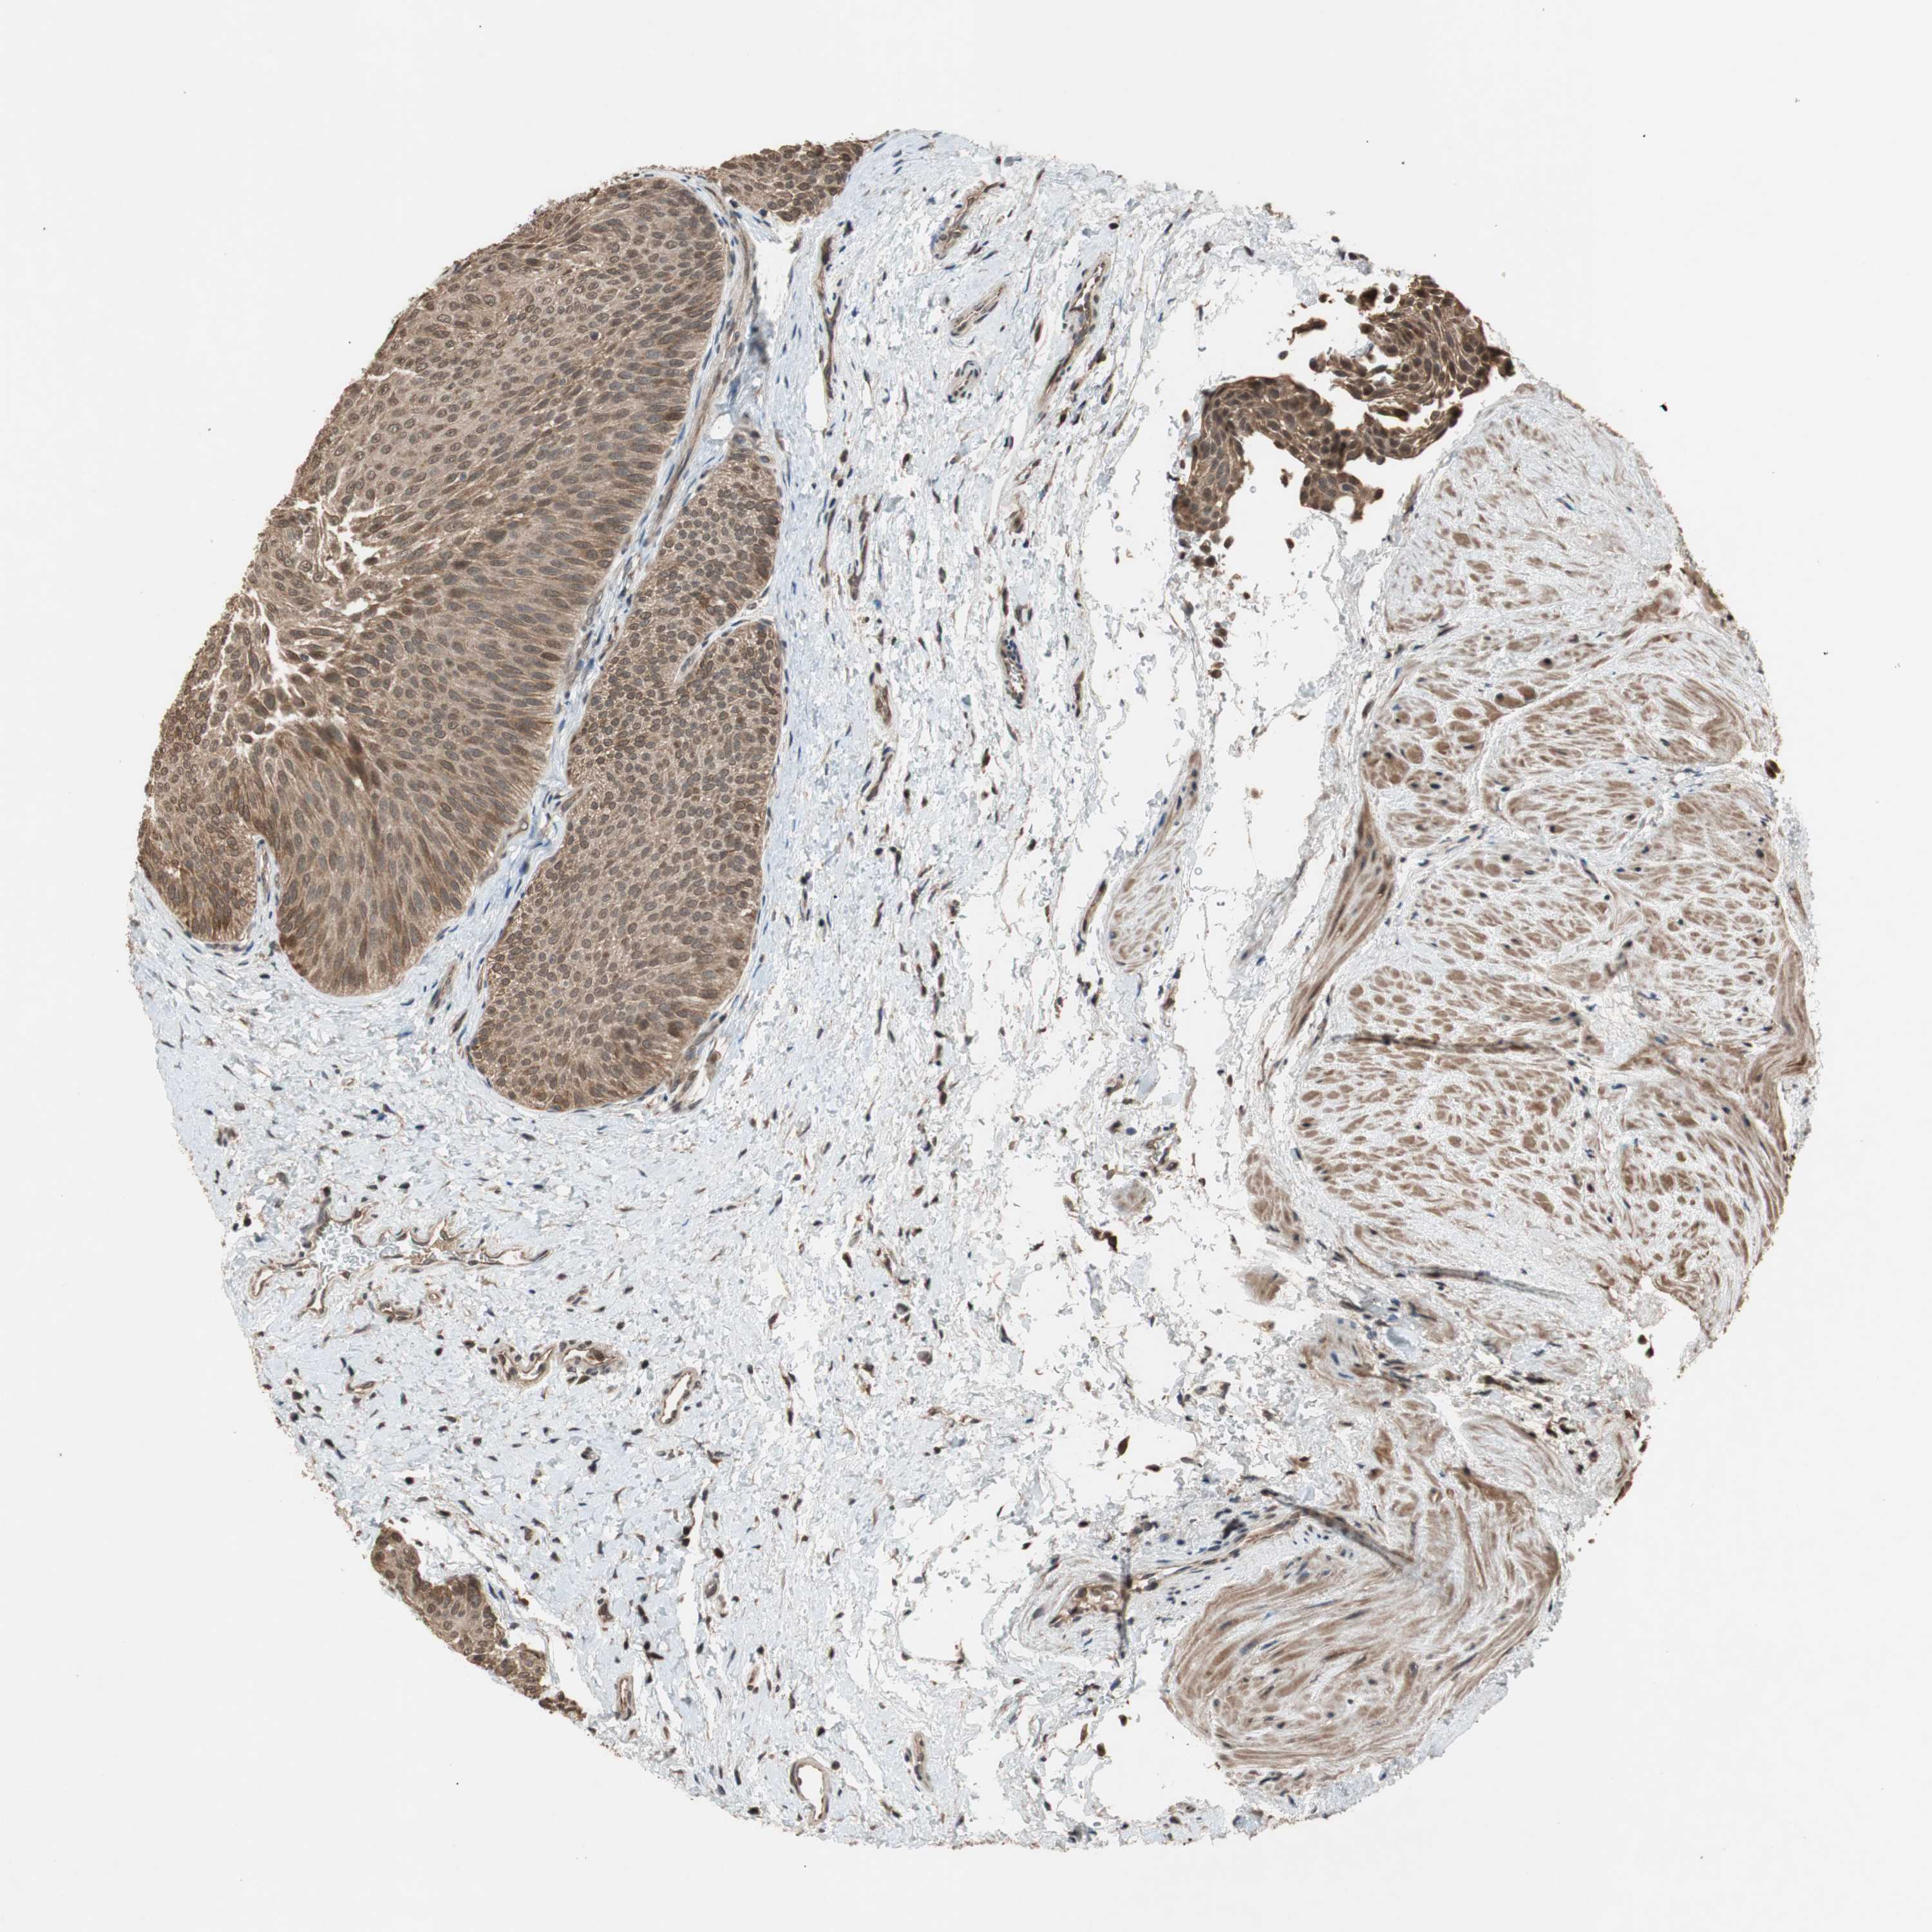

UROTHELIAL CANCER - Protein expressioni

A mouse-over function shows sample information and annotation data. Click on an image to view it in a full screen mode. Samples can be filtered based on level of antibody staining by selecting one or several of the following categories: high, medium, low and not detected. The assay and annotation is described here.

Note that samples used for immunohistochemistry by the Human Protein Atlas do not correspond to samples in the TCGA dataset.

Antibody stainingi

Antibody staining in the annotated cell types in the current human tissue is reported as not detected, low, medium, or high, based on conventional immunohistochemistry profiling in selected tissues. This score is based on the combination of the staining intensity and fraction of stained cells.

Each image is clickable and will lead to virtual microscopy that enables deeper exploration of all samples and also displays staining intensity scores, fraction scores and subcellular localization as well as patient and tissue information for each sample.

Antibody HPA009078

Staining

High

Medium

Low

Not detected

Intensity

Strong

Moderate

Weak

Negative

Quantity

>75%

75%-25%

<25%

None

Location

Nuclear

Cytoplasmic/membranous

Cytoplasmic/membranous,nuclear

Urothelial carcinoma, Low grade

Urothelial carcinoma, High grade